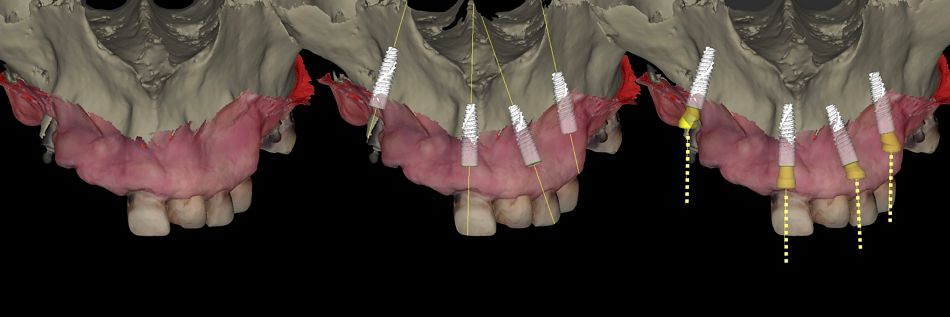

• Segmentation of the bone using AI and superimposition of the intraoral scan file (Fig. 12).

Fig. 12

• Positioning of implants and Novaloc® abutments (Fig. 13).

Fig. 13

• Superimposition of dental setup coming from Smilecloud (Fig. 14).

Fig. 14

• Implant placement and Novaloc® abutment realignment following the ideal prosthetic axis (Fig. 15).

Fig. 15

• Detailed prosthetic realignment confirmed in coDiagnostiX® (Fig. 16).

Fig. 16